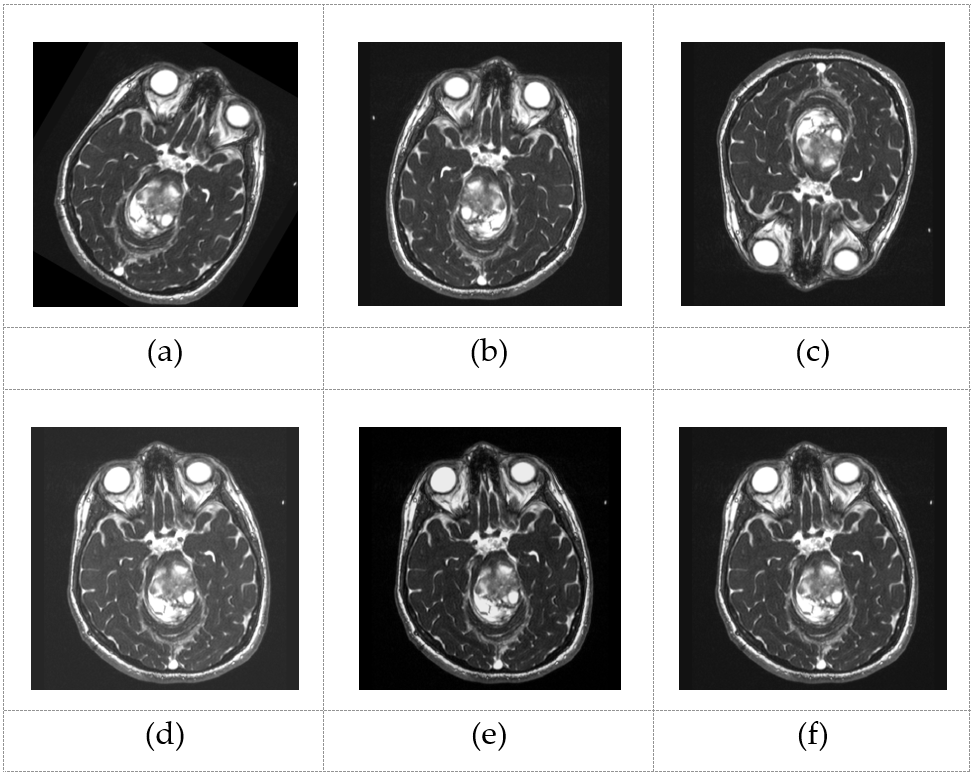

6. To enhance the diversity of our training samples and proactively mitigate the risk of overfitting while having more control over the data preparation process, we developed a tailored data augmentation class utilizing Python’s built-in libraries. This augmentation class encompassed modifications such as brightness intensity adjustments, rotations, as well as vertical and horizontal flips, all while ensuring the corresponding bounding boxes (the rectangular area indicating the tumor tissue) were appropriately adjusted. The execution of the data augmentation pipeline has led to a substantial expansion in the overall data set volume, all while preserving its initial distribution. This augmentation procedure has contributed to enhancing and diversifying our training data, resulting in an overall improvement in data quality.

Refer to caption

Figure 2: Outputs of the augmentation module for a random MRI sample. (a) Rotated sample; (b) Horizontally flipped sample; (c) Vertically flipped sample; (d) Brightened sample; (e) Dimmed sample, (f) Normal sample.